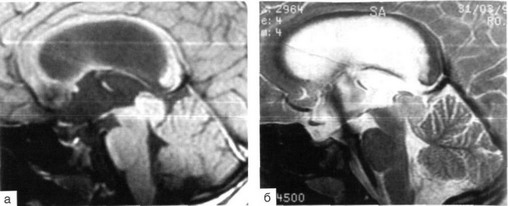

Рис. 37-7. Рентгеновская и эндоскопическая анатомия структур дна и задних отделов III желудочка при постменингитическом стенозе водопровода у 5-летнего ребенка.

Вверху: "-взвешенный сагиттальный срез головы. Признаки очень давней окклюзионной водянки с уплощением инфундибулярной части III желудочка и дивертикулом в направлении супрапинеального кармана и четверохолмной цистерны. Водопровод стенозирован на всем протяжении. Внизу: эндоскопическая картина задних отделов III желудочка (эндоскоп проведен туда сквозь отверстие Монро, оптика 30°, угол зрения указан стрелкой на МРТ-изображении). Треугольник указывает на стенози-рованное устье водопровода, длинные белые стрелки - на заднюю комиссуру, черная стрелка - на сосудистое сплетение III желудочка.